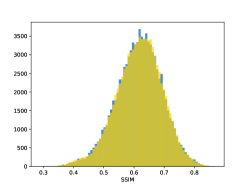

To visualise similarity metrics that compare image pairs (RMSE, SRE, SSIM) two metric distributions are generated: intra-similarity and inter-similarity. For each compared sample 300 random images are selected. The inter-similarity distribution is calculated for each image pair combination from both compared samples e.g. generated images of COVID-19 and real images of COVID-19. For the intra-similarity, all pairs of images in a single sample e.g real images of COVID-19 are considered. By comparing the shape of intra-similarity for the training subsample (Dataset) with the inter-similarity of training and generated samples the quality of the generated sample can be judged. It is also possible to compare in this way between the four image classes present in the dataset. The resulting distributions of inter-similarity of COVID-19 and the three remaining classes are compared in Fig. 4 to distributions of intra-similarity of the COVID-19 sample for each metric. All metrics, as expected based on available medical evidence Rubin et al. (2020), indicate that there are visible differences not only between COVID-19 and normal samples but also between viral pneumonia and lung opacity. Therefore, all classes should be distinguishable.

To visualise differences between synthetic and real samples distributions are generated for each of the RMSE, SRE and SSIM metrics: intra-similarity and inter-similarity. For each compared sample 300 random images are selected. The inter-similarity distribution is calculated for each image pair combination from both compared samples e.g. generated images of COVID-19 and real images of COVID-19. For the intra-similarity, all pairs of images in a single sample e.g real images of COVID-19 are considered. The distributions for generated samples describe very well the distributions for corresponding real images as shown in Fig. 6.

The quality of generated images is also confirmed with classical similarity metrics. The distributions of those similarity measures between generated and real images are compared for each sample with the distribution obtained within the real samples 6. The distributions for generated samples describe very well the distributions for corresponding real images. For an example see the results for the SSIM metric presented in Fig. 10. The small visible differences are almost insignificant compared to differences observed between the classes in Fig. 4.